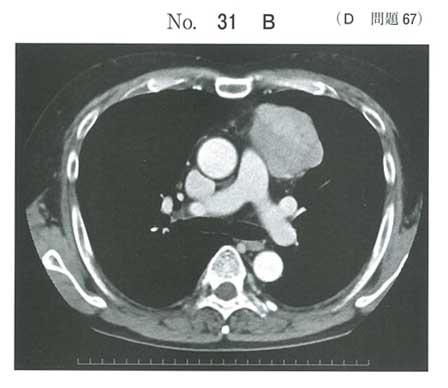

| タイトル:113D-67 | コメント数:5 | チョイ割 |

重症筋無力症+胸腺腫。確か過去の国試で赤芽球癆の合併は出ていたような…

低ガンマグロブリン血症を伴う胸腺腫→Good 症候群だったと思います